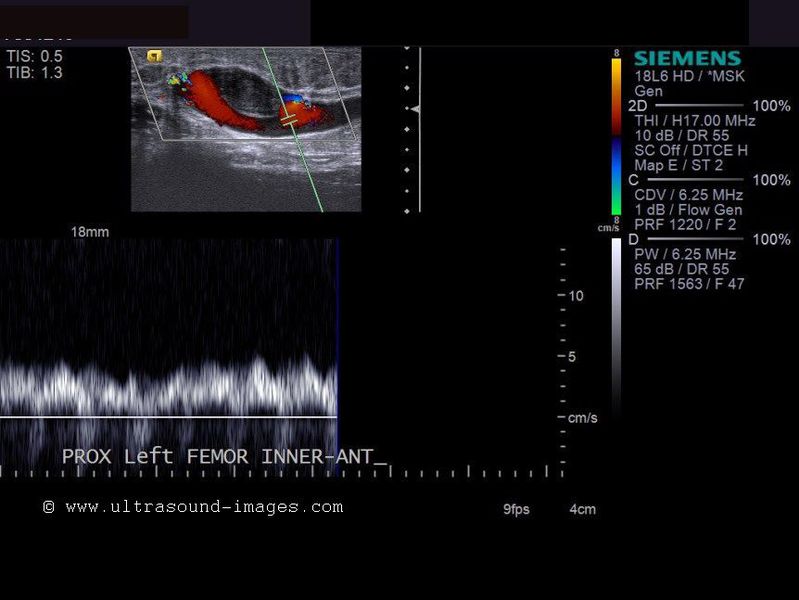

Femoral vein thrombus

The above color Doppler ultrasound and spectral Doppler imaging of the left femoral vein show a large echogenic lesion in the anterior wall of the vein. There is evidence of partial obstruction of blood flow within the femoral vein, with a thin stream flowing around the obstructive lesion. This appearance is diagnostic of a thrombosis, with partial obstruction of the left femoral vein. Ultrasound and color Doppler images are courtesy of Mr. Shlomo Gobi, Israel.